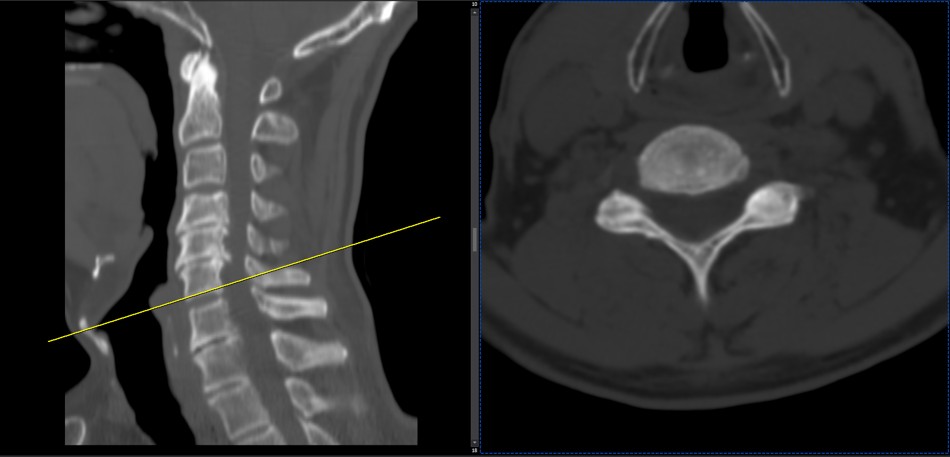

30 year old patient of mine with R. IVF disc extrusion of C 5-6 with R upper extremity pain and numbness without neurological deficit was suggested to have urgent surgery

in his EMG. NCV didn’t have any active axonal loss

got 20 sessions of chiropractic care in one month by me mainly using decompression and C0-C1 prone drop manipulation and 3 sessions of mild adjustment to segments above disc herniation. No direct adjustment to the involved disc extrusion

After treatment:

reduction of R. IVFdisc extrusion by more than 50%.

90% improvement in patient’s signs and symptoms and preventing of unnecessary expensive surgery

following one month of cervical chiropractic spinal treatments